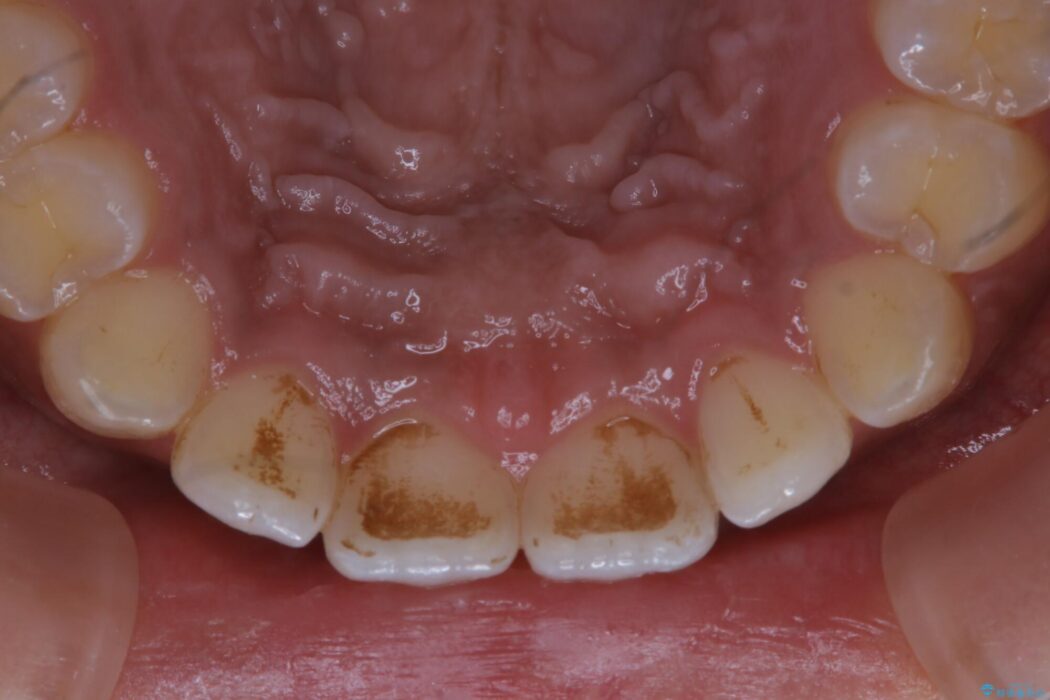

【20代女性】タバコのヤニ(ニコチン、タール)を徹底的に除去

タバコによって付着したステインを綺麗にしたいとのことで来院されました。

ステインがこびりついていたため、PMTC60分コースを行いました。

タバコに含まれているタールが歯の黄ばみの原因になります。その黄ばみなどを、無理に落とそうとしたりすると歯の表面に傷がついてしまったり余計に汚れがつきやすい状態になることがあります。

PMTCでは、専門の機材を使用し、歯の表面の凸凹にミネラルを補給して、ツルツルの表面に仕上げます。定期的にPMTCを行うことにより、歯質の強化になり着色がつきにくい状態になります。